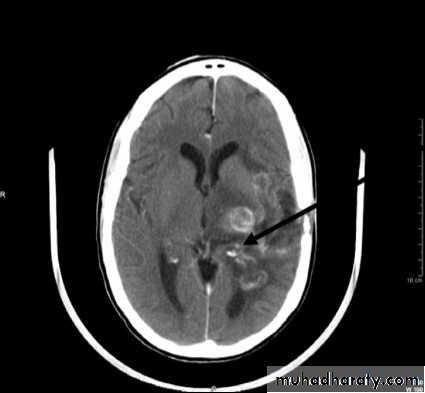

Primary CNS lymphoma

B lymphocytesIncreased ICP

Brain destruction

• Computed Tomography scan (CT scan) with/without contrast• Magnetic Resonance Imaging (MRI) with/without contrast